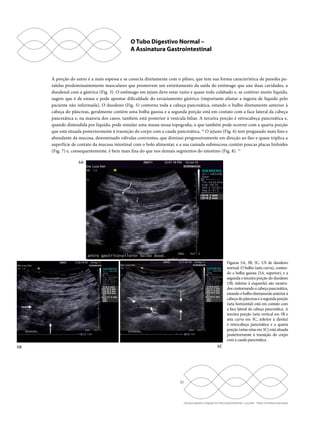

Figuras 4A, 4B, 4C, 4D. Estômago identificado pela ingesta hídrica. Em estômago colabado após jejum de 12 horas (4A, superior à

esquerda), durante a ingestão de água, o líquido que cai na cavidade gástrica tem aspecto ecogênico (4B, superior à direita), devido

à presença de múltiplas partículas gasosas que se misturaram ao líquido durante a ingestão e dificultam a identificação da parede

gástrica posterior; após 5 minutos da ingesta hídrica (4C, inferior à esquerda), as partículas gasosas se desprenderam do líquido, que

se torna quase anecoico, e todas as paredes estomacais estão bem delineadas. Pequena quantidade de líquido de estase pode estar

presente no estômago (setas) do paciente em jejum (4D, inferior à direita).

A porção do antro é a mais espessa e se conecta diretamente com o piloro, que tem sua forma característica de paredes pa-ralelas

predominantemente musculares que promovem um estreitamento da saída do estômago que une duas cavidades, a

duodenal com a gástrica (Fig. 3). O estômago em jejum deve estar vazio e quase todo colabado e, se contiver muito líquido,

sugere que é de estase e pode apontar dificuldade do esvaziamento gástrico (importante afastar a ingesta de líquido pelo

paciente não informada). O duodeno (Fig. 5) contorna toda a cabeça pancreática, estando o bulbo diretamente anterior à

cabeça do pâncreas, geralmente contém uma bolha gasosa e a segunda porção está em contato com a face lateral da cabeça

pancreática e, na maioria dos casos, também está posterior à vesícula biliar. A terceira porção é retrocabeça pancreática e,

quando distendida por líquido, pode simular uma massa nessa topografia, o que também pode ocorrer com a quarta porção

que está situada posteriormente à transição do corpo com a cauda pancreática. 12 O jejuno (Fig. 6) tem pregueado mais fino e

abundante da mucosa, denominado válvulas coniventes, que diminui progressivamente em direção ao íleo e quase triplica a

superfície de contato da mucosa intestinal com o bolo alimentar, e a sua camada submucosa contém poucas placas linfoides

(Fig. 7) e, consequentemente, é bem mais fina do que nos demais segmentos do intestino (Fig. 8). 12